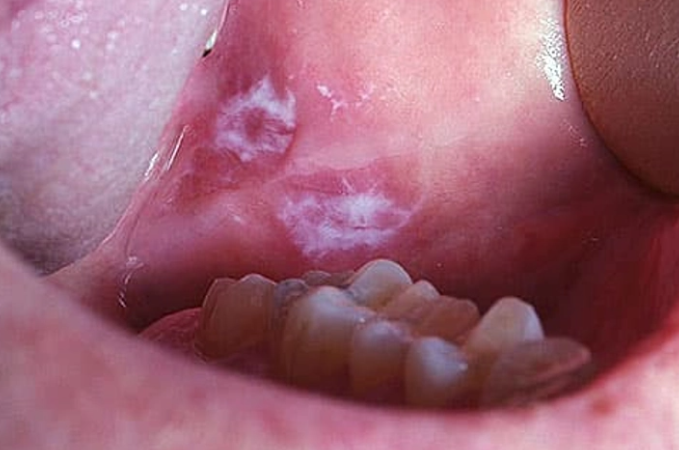

**점액낭종(Mucocele)**은 입안의 **작은 침샘(소타액선)**이 손상되어 점액이 조직 내에 고이면서 생기는 무통성 물혹입니다.

항목 내용 발생 부위 입술 안쪽, 혀 밑, 뺨 안쪽 점막 등 색상 투명~흰색, 연보라색 또는 약간 파란빛 촉감 말랑말랑하고 부드럽지만 눌러도 아프지 않음 크기 보통 0.5cm~1.5cm, 커지기도 함 👉 겉으로는 수포나 궤양처럼 보일 수 있어 오해하기 쉽지만, 점액낭종은 염증이나 바이러스성 감염과는 다릅니다.